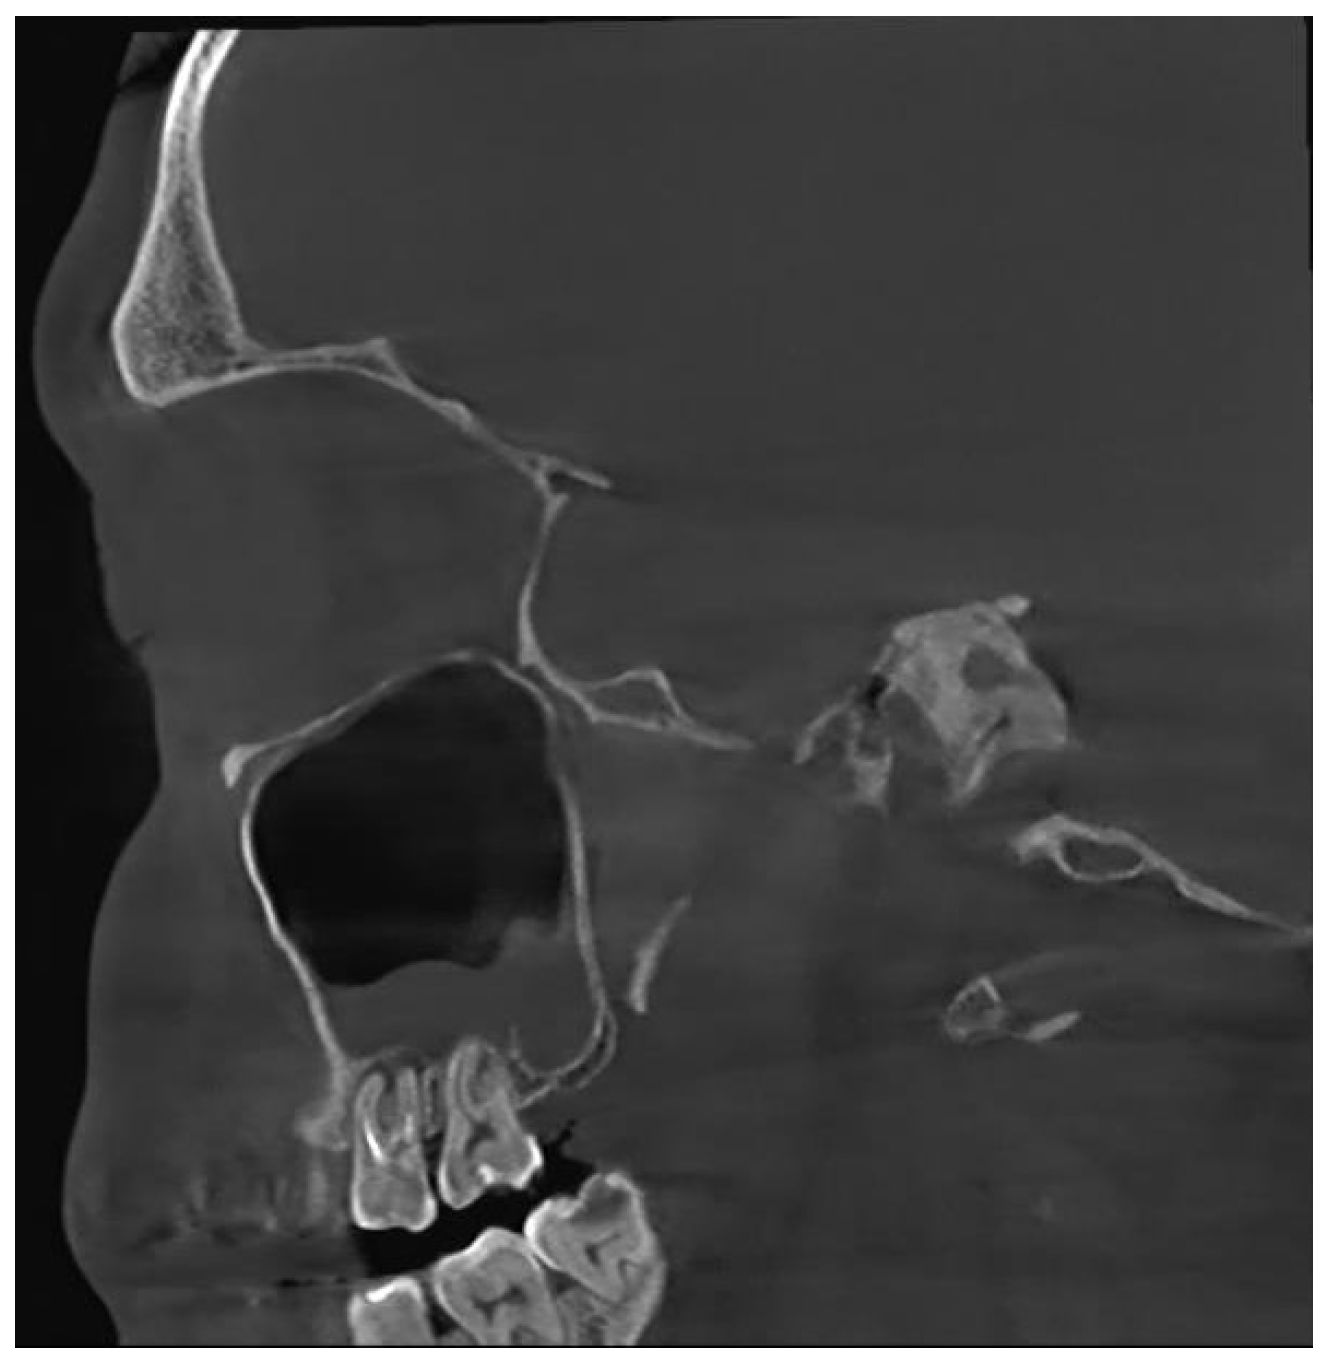

Figure 7. CBCT image of bilateral maxillary sinusitis caused by blade implants; chronic OAF (oroantral fistula) next to the implants. ((A): coronal, (B): sagittal, (C): axial view).

Among the patients, 63 (58%) did not have previous dental treatment performed by other physicians before the development of OS, while 48 (42%) mentioned previous dental intervention. Extraction was the most common dental procedure (27%), followed by root canal treatment in six patients (5%), sinus closure in three patients (3%), implant placement (Figure 7) and root apex resection in two patients each (2%).